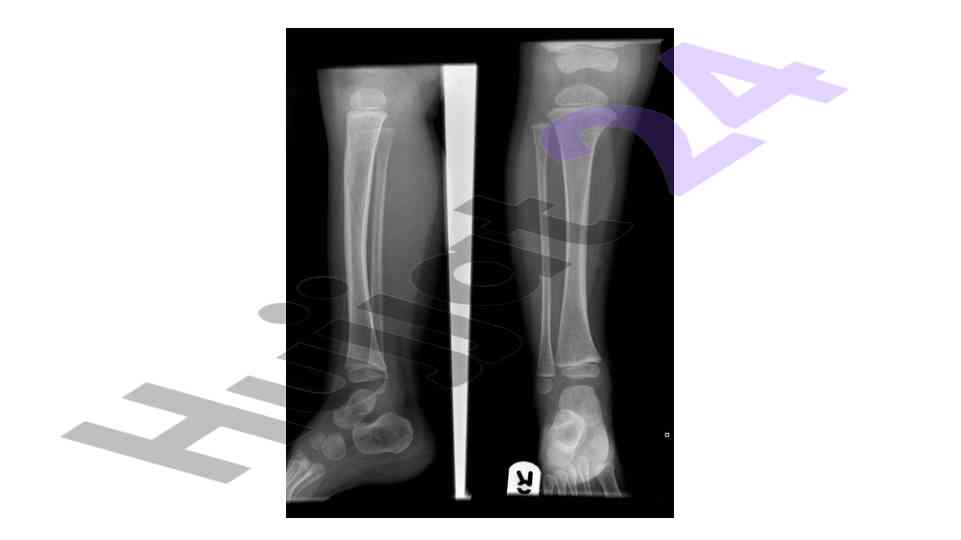

An overview of the muskuloskeletal system with a focus on pediatric applications and implications for treatment.